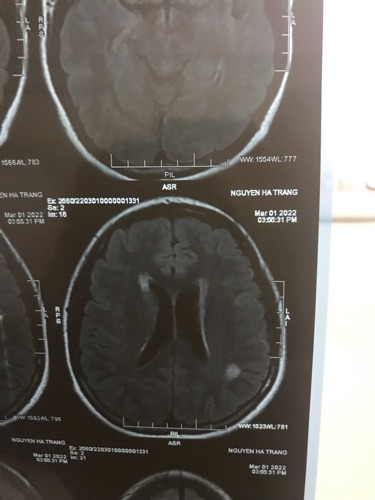

Em chào các bác sĩ ạ. Nay em có đi khám về hậu covid do thường xuyên mất ngủ , khó thở thì được bác sĩ khám nội phát hiện ra hình ảnh chụp MRI có tổn thương nghi ngờ viêm não nhưng do không phải chuyên môn nên bác sĩ khuyên em nên khám chuyên khoa thần kinh, khả năng cao chỗ viêm có từ trước khi em bị covid Em cần nhờ bác sĩ bên mình khoa thần kinh xem giúp em với ạ và nếu khám thì khám viện nào tại HN được ạ. Em cảm ơn ai